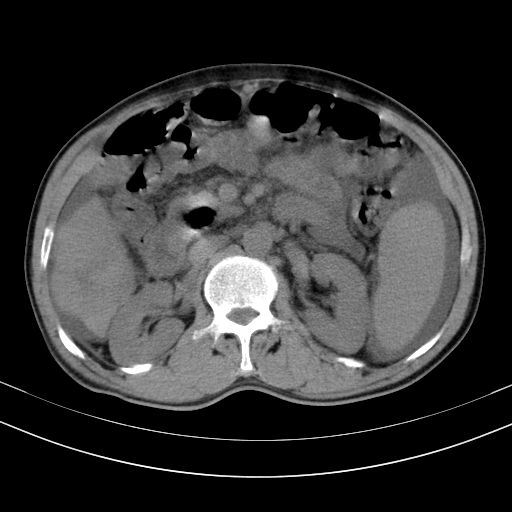

以下是引用随光逐影在2010-2-28 10:23:00的发言:[br]1)考虑肝癌;建议行ct增强扫描检查。2)肝硬化,脾大,腹水。3)慢性胆囊炎。

以下是引用dyqct在2010-2-28 16:44:00的发言:[br][quote]以下是引用随光逐影在2010-2-28 10:23:00的发言:[br]1)考虑肝癌;建议行ct增强扫描检查。2)肝硬化,脾大,腹水。3)慢性胆囊炎。